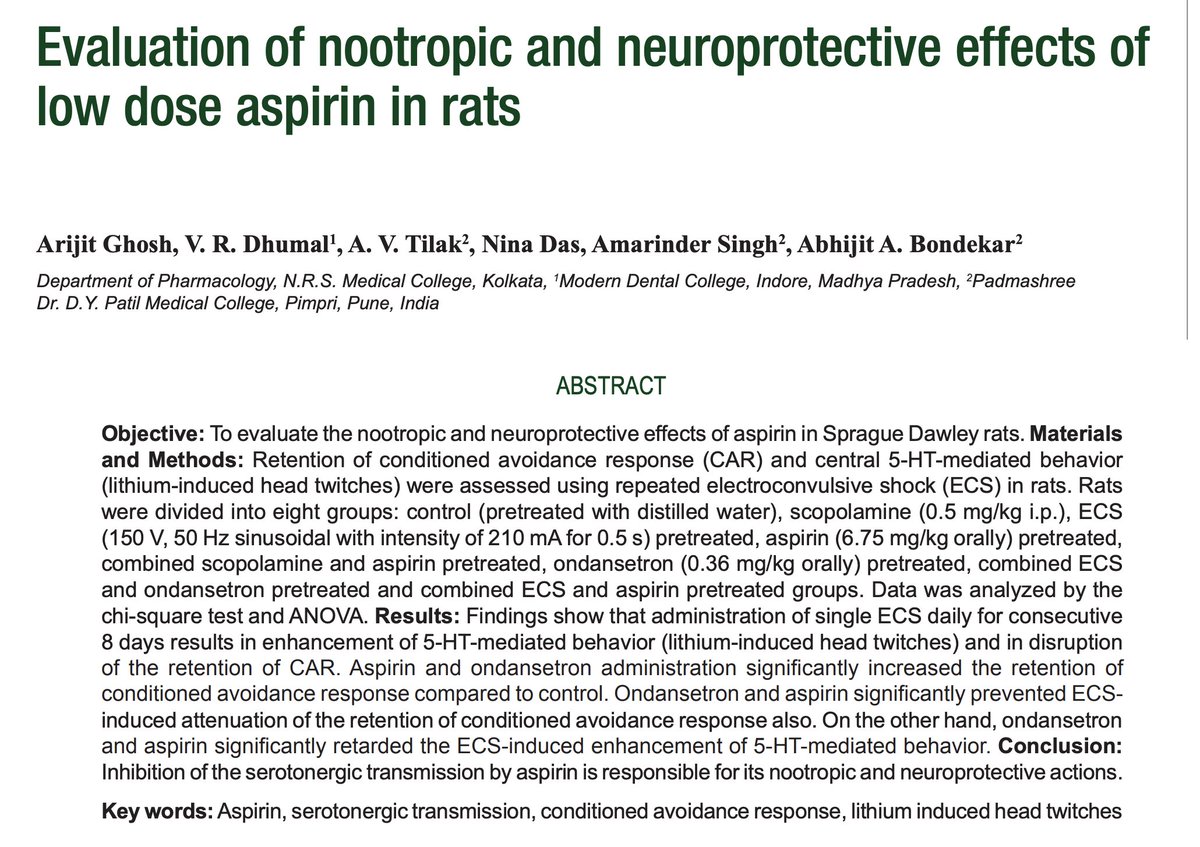

Aspirin has also been shown to act as a nootropic.

Elevated serotonin in the brain can cause neurological abnormalities, but aspirin counteracts this.

Use of aspirin has been shown to dramatically cut down the risk of developing dementias, cutting some down by over half!

Elevated serotonin in the brain can cause neurological abnormalities, but aspirin counteracts this.

Use of aspirin has been shown to dramatically cut down the risk of developing dementias, cutting some down by over half!